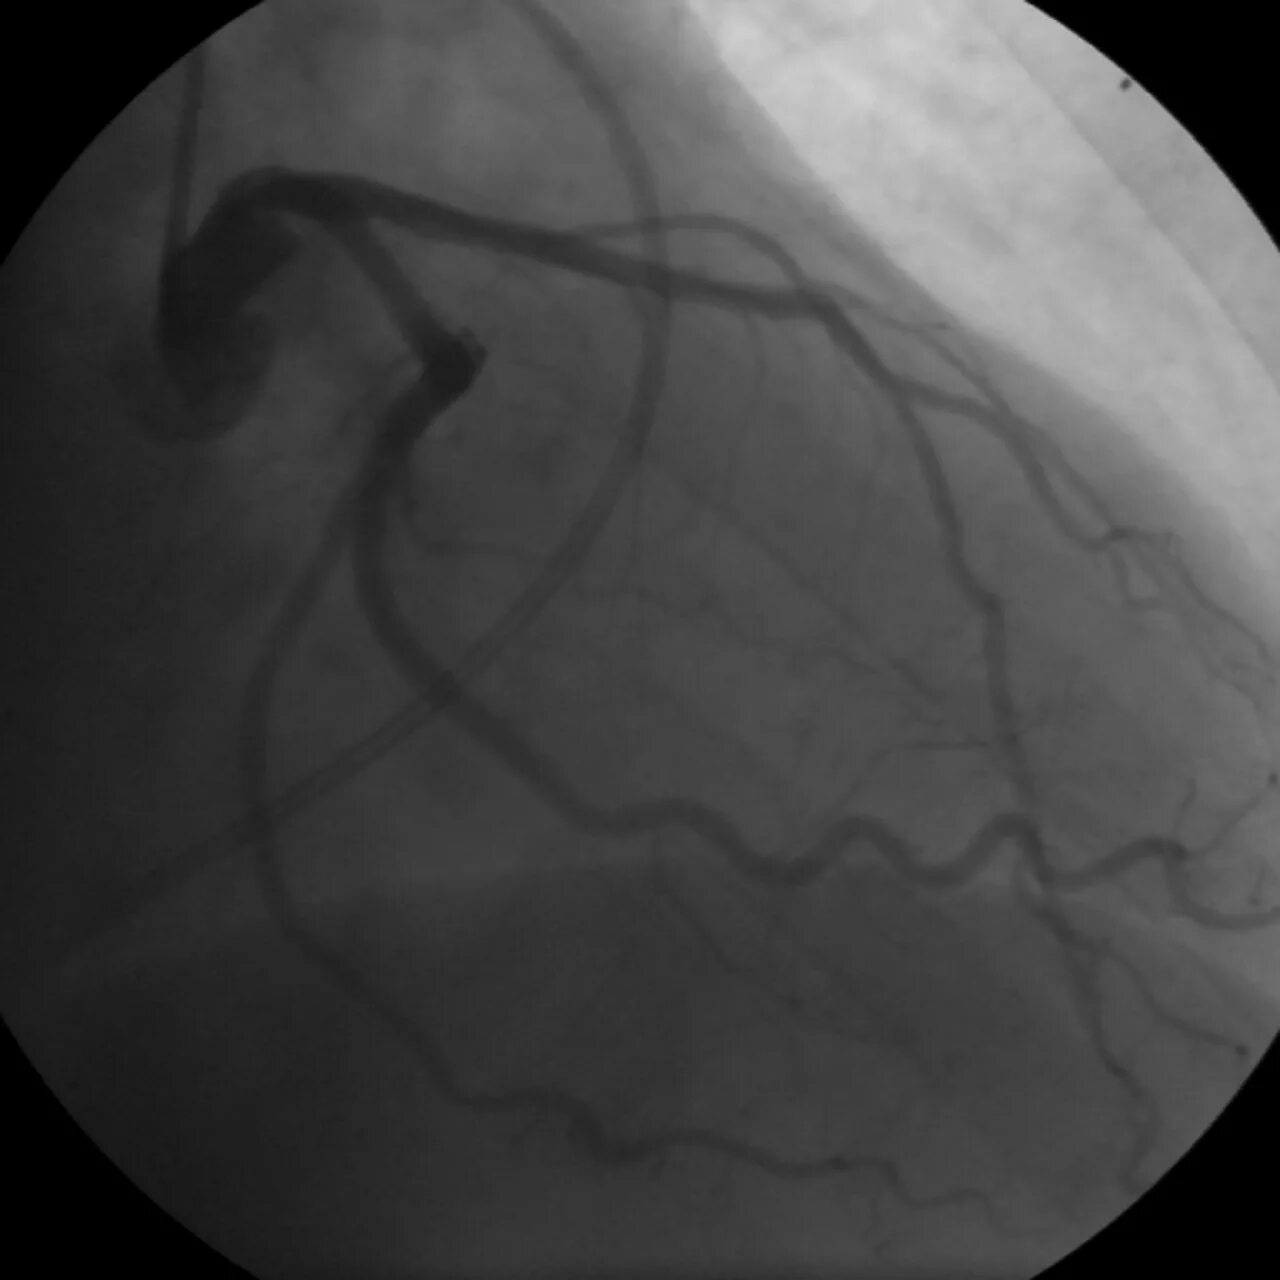

Атеросклероз левой коронарной артерии